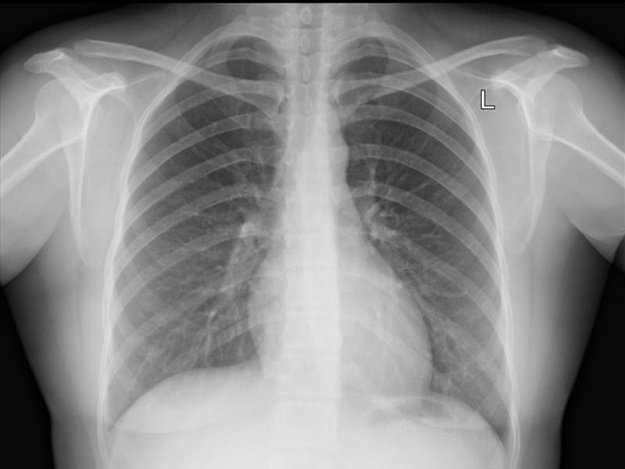

Легкие

Легкие ответственны за газообмен между воздухом и кровью. Хотя они и не часто вызывают боли в животе, заболевания, поражающие основание легких, могут повлиять на плевру (оболочку вокруг легких) и диафрагму, что может привести к синдрому. Сами легкие не дают ощущение боли, если не затрагиваются окружающие их структуры. Заболевания:

- Пневмония — бактериальная или вирусная.

- Плеврит — воспаление оболочки легких.

- Легочная эмболия — сгустки крови в легких.

Врачи: пульмонолог, сосудистый хирург.